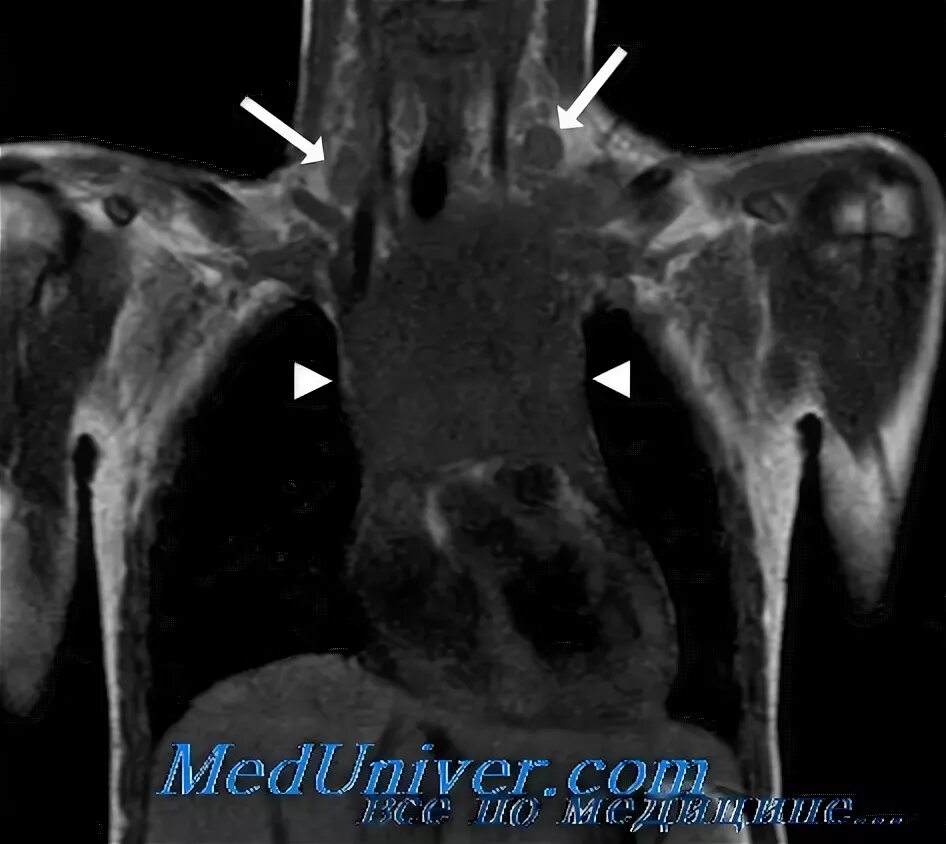

Мрт сигнал